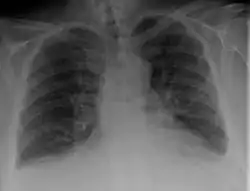

Chest X-ray

Chest X-rays are frequently used to aid in the diagnosis of CHF. In a person who is compensated, this may show cardiomegaly (visible enlargement of the heart), quantified as the cardiothoracic ratio (proportion of the heart size to the chest). In left ventricular failure, there may be evidence of vascular redistribution ("upper lobe blood diversion" or "cephalization"), Kerley lines, cuffing of the areas around the bronchi, and interstitial edema. Ultrasound of the lung may also be able to detect Kerley lines.[39]

Congestive heart failure with small bilateral effusions.

Kerley b lines.